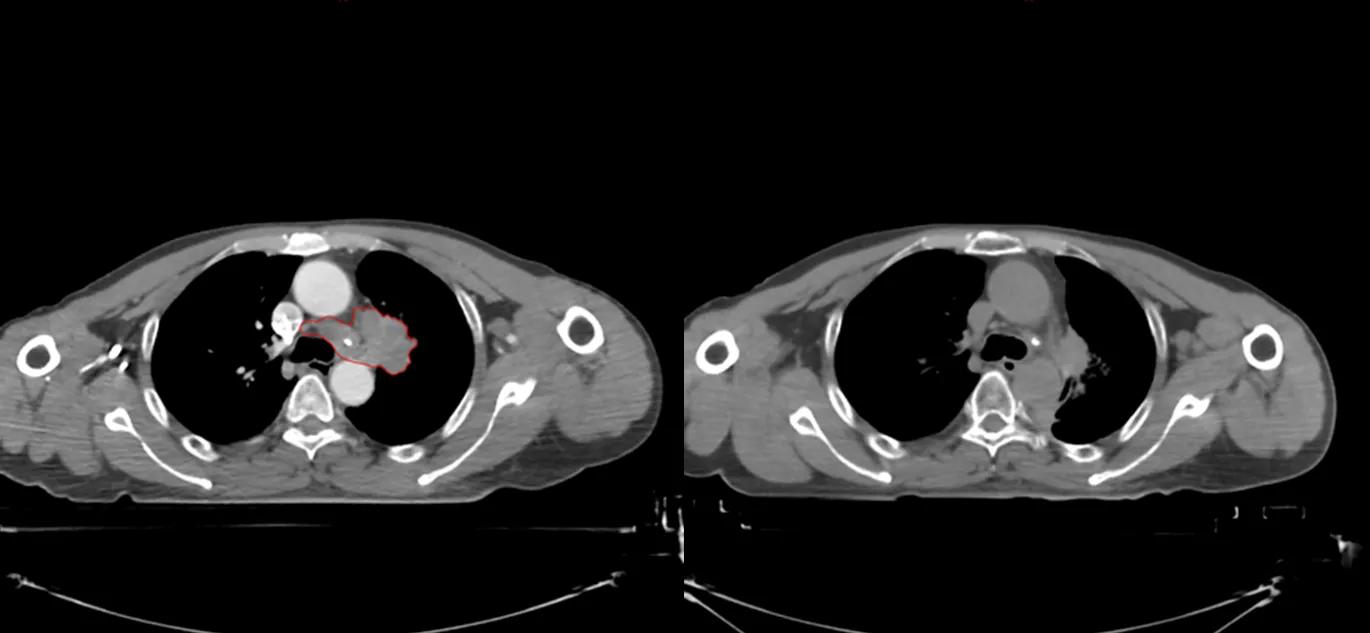

与这些名人患肺癌的同时,笔者治好了至少5位晚期肺癌病人(见下图CT片显示的肿瘤)。笔者病人有咳嗽,咯血,胸痛,胸闷,气急等症状,病人家属知道亲人是晚期肺癌,没有抱多大希望,治疗的目的只是想减轻一些症状,延长生命。经过笔者的精心治疗,2例现已活了5年多,2例已活过3年多,1例已活过2年多。治疗时年龄最大有82岁,最小年龄51岁,他们现在都生活得很好,甚至一个来自江西农村的病人一直在田地里干重体力农活。

治疗前后CT片对比,红色为肿瘤(左),治疗后肿瘤消失(右)